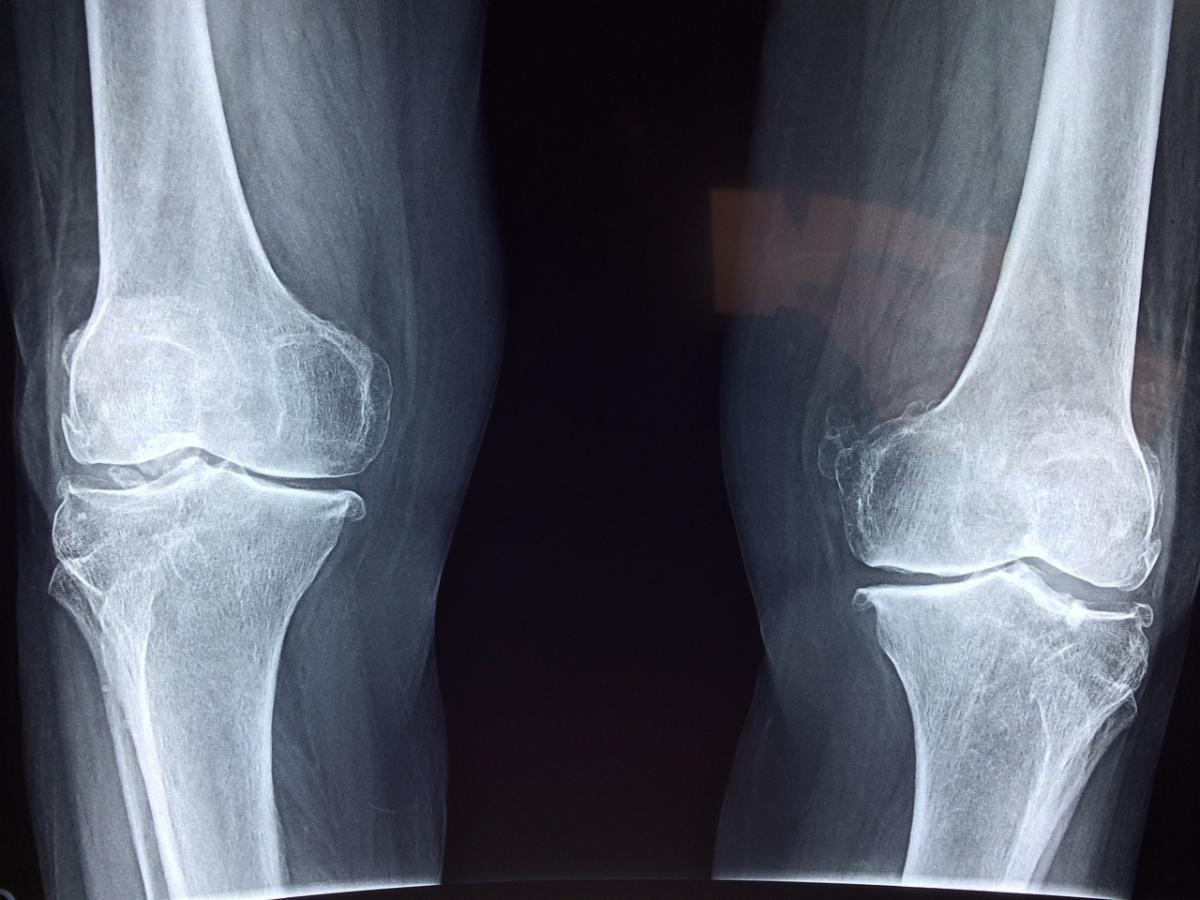

Earlier this month, Wan-Ju Li, PhD, associate professor in the UW Department of Orthopedics and Rehabilitation, and his research team were awarded a prestigious $500,000 Research Forward grant to support a bold new project that integrates cutting-edge science and engineering to tackle one of the biggest challenges in healthcare – osteoarthritis.

Affecting over 32 million Americans, osteoarthritis is a leading cause of chronic pain and disability, with current treatments providing only limited long-term relief. Although joint replacement surgery can restore function, the procedure involves the removal of damaged cartilage and bone and the replacement of these tissues with metal and plastic implants. This approach is highly invasive, costly, and comes with risks such as infection, implant failure, and lengthy recovery periods.

Dr. Li and his team are developing a novel, minimally invasive method that utilizes advanced ultrasound technology to bioprint engineered cartilage implants directly within the body, eliminating the need for open surgery. The technique uses real-time, AI-powered imaging to guide the precise construction of tissue at the site of damage. By minimizing the need for open surgery, it offers a safer, more targeted approach that could lead to better healing outcomes.